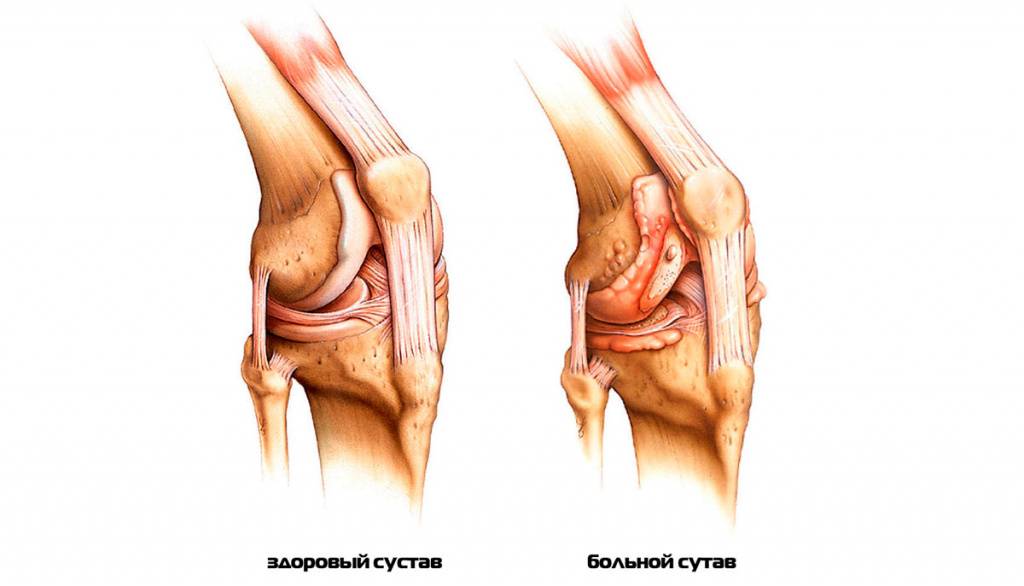

Чтобы понять механизм возникновения хруста в суставах, нужно вспомнить азы анатомии. По строению суставы в организме человека напоминают шарниры: в них одна кость скользит по поверхности другой. Головки костей гладкие и подогнаны по форме друг к другу: это необходимо для хорошего скольжения. Между ними находится суставная жидкость, которая играет роль своеобразного «машинного масла» для суставов. Чтобы она не вытекала наружу, кости покрыты суставными хрящами. Они же обеспечивают внешнюю целостность суставов.

Внутри капсулы, образованной хрящами, циркулирует та самая суставная жидкость. В капсулу также вплетены связки, которые повышают прочность всего суставного механизма. А между некоторыми костями, головки которых прилегают друг к другу неидеально, есть специальные прокладки – мениски.

Артрит. Воспалительный процесс в суставе приводит к расслоению, истончению и трещинам хрящевой ткани. Если заболевание не лечить, изменения со временем затрагивают и кость: на ней появляются наросты, уплотнения и шипы. Далее происходит деформация кости, из-за чего возникают отеки и сильные боли даже в состоянии покоя.

- Артрит (воспаление одного или нескольких суставов). Изменения в хрящевой ткани при артритах проявляется трещинами, расслоением, истончением, что приводит к появлению скрипения при движениях в суставе. Кроме того, хруст и треск связаны с изменениями в костной ткани — появлением уплотнений, шипов, наростов.